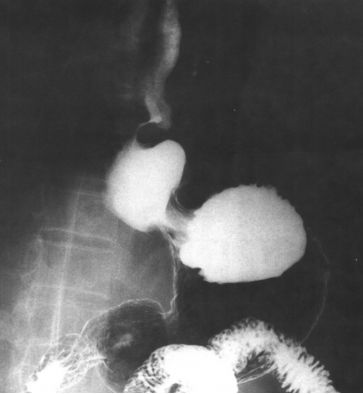

食管裂孔疝:膈上疝囊。

食管裂孔疝有4种:短食管型、食管旁型、混合型、滑动型,每型都有不同的表现,但最直接的还是膈上疝囊。

食管裂孔疝的造影检查分别如下:

短食管型食管裂孔疝

短食管型食管裂孔疝(不可回复性)

不可复性食管裂孔疝